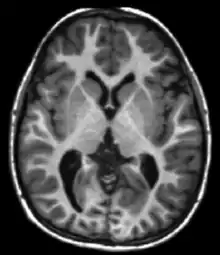

| Spin echo | T1 weighted | T1 | Measuring spin–lattice relaxation by using a short repetition time (TR) and echo time (TE). |

Standard foundation and comparison for other sequences |

![]() |